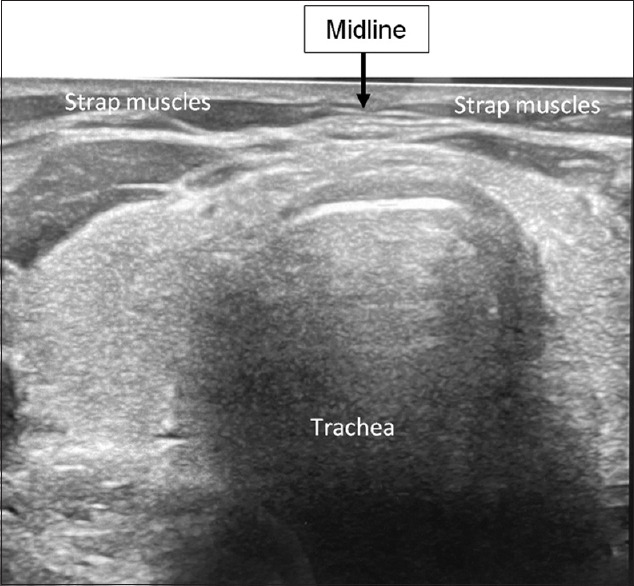

Abstract: Endoscopic thyroidectomy is a minimally invasive surgical approach that has become popular due to its cosmetic advantages and reduced post-operative discomfort. Central to the success of this procedure is the accurate identification of the midline, which becomes a challenge in endoscopic surgeries. We propose a novel method of using methylene blue, a Food and Drug Administration-approved dye, which offers the ability to clearly mark the midline, enhancing orientation and reducing the potential for injury to critical anatomical structures. Although using methylene blue has many benefits, there are drawbacks, including the requirement for intraoperative ultrasonography. Continued research and clinical experience will be critical in improving and extending its use in the field of thyroid surgery.